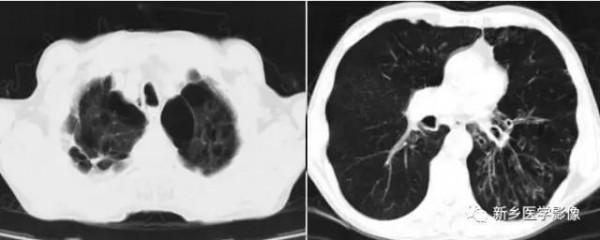

肺空腔CT圖;a、CT肺窗顯示兩上肺大泡;b、CT肺窗顯示左下支氣管擴張